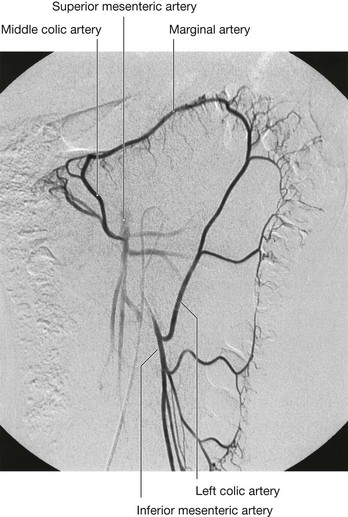

The gastrointestinal system and its derivatives are supplied by three major arteries

Three large unpaired arteries branch from the anterior surface of the abdominal aorta to supply the abdominal part of the gastrointestinal tract and all of the structures (liver, pancreas, and gallbladder) to which this part of the gut gives rise to during development (Fig. 4.17). These arteries pass through derivatives of the dorsal and ventral mesenteries to reach the target viscera. These vessels therefore also supply structures such as the spleen and lymph nodes that develop in the mesenteries. These three arteries are:

image the celiac artery, which branches from the abdominal aorta at the upper border of vertebra LI and supplies the foregut;

image the superior mesenteric artery, which arises from the abdominal aorta at the lower border of vertebra LI and supplies the midgut; and

image the inferior mesenteric artery, which branches from the abdominal aorta at approximately vertebral level LIII and supplies the hindgut.

Fig. 4.17 Blood supply of the gut. A. Relationship of vessels to the gut and mesenteries. B. Anterior view.